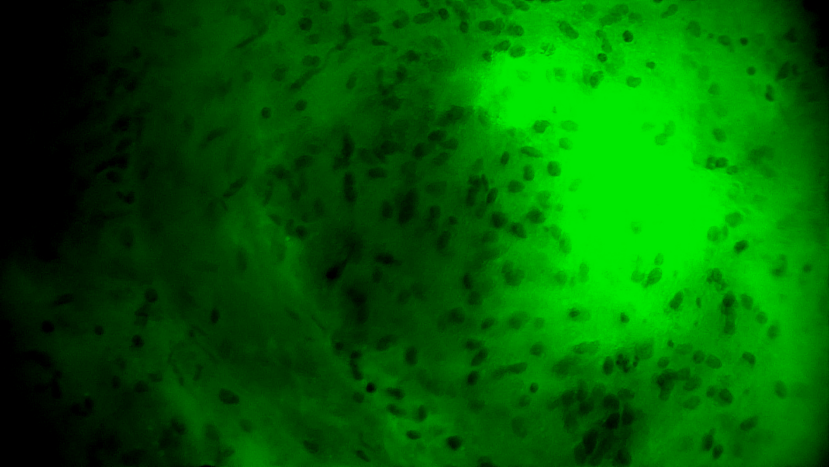

術(shù)中EndoSCell?細(xì)胞圖像如下:

腫瘤中心區(qū)域:細(xì)胞核異型性顯著,分布密集且不規(guī)則,陽(yáng)性。

腫瘤邊緣區(qū)域:個(gè)別細(xì)胞核存在異型性,密度下降,分布不規(guī)則,陽(yáng)性。

正常細(xì)胞組織:細(xì)胞核形態(tài)正常,分布均勻,陰性。